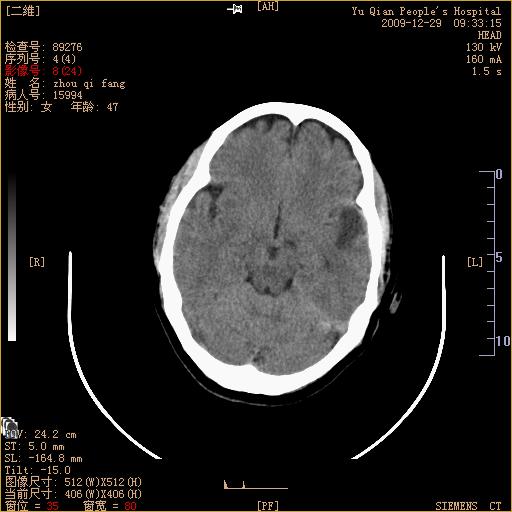

头部外伤后1天   请看看左侧丘脑外侧原是否为小血肿?(两天表现大致相仿。)谢谢

左颞叶前外部见片状挫裂伤,左丘脑小血肿;颅板下见多发小片状血肿影,两侧额部见少量蛛网膜下腔出血,

左额叶颅内板下也有一高密度灶。。。考虑多发小灶性出血(挫裂伤)。。。复查后再定

不好定。同时左侧裂池形态异常,左侧豆状核点状高密度,第四幅右额叶稍高密度影,最后一幅左额叶颅骨内板下方小片状高密度影。复查。